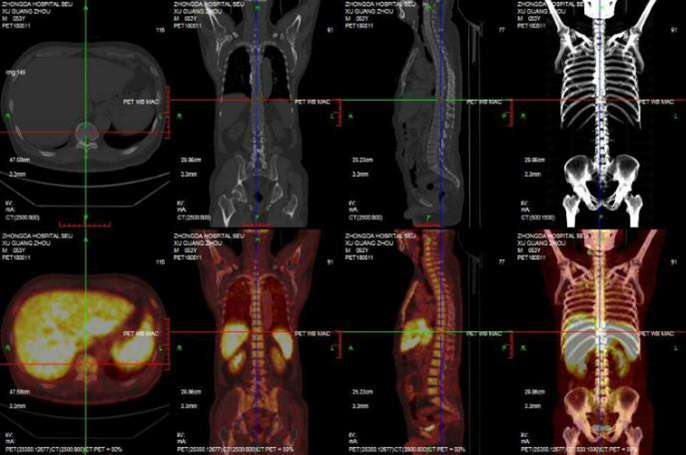

PET-CT检查结论:肝左内叶稍低密度影,FDG代谢不均匀性增高,考虑恶性病变可能,右侧颈部多枚稍肿大淋巴结,FDG代谢均增高,考虑肿瘤转移可能性大,全身骨弥漫性FDG代谢增高,双侧肾上腺结节样增粗、肝脾略大、两肺多发斑片及结节影,FDG代谢均增高,考虑感染性病变可能,腔气间隙、双肺门多枚淋巴结FDG代谢均增高,考虑炎性淋巴结可能,盆腔右前方肠管局限性FDG代谢增高考虑炎性或生理性摄取可能(图4)

图4  PET-CT肝脾略大,肝左内叶稍低密度影,FDG代谢不均匀性增高